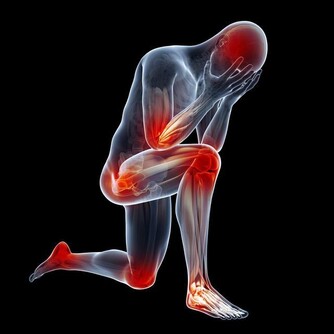

目前,患痛風的人越來越多,尤其是很多年輕人,不健康的生活習慣導致尿酸值越來越高,痛風發作的時候嚴重影響生活質量。然而,很多的痛風患者只是在盲目的降尿酸,並沒有弄清楚自己的尿酸為什麼會高,